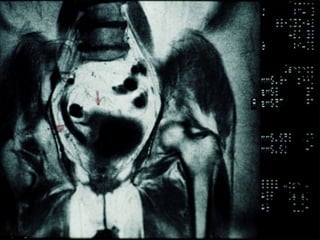

Câncer de Bexiga Estudos de imagens Diagnóstico Ultrassonografia Urografia excretora Estadiamento CT RNM Rx tórax  Cistoscopia + biópsia + biópsias randomizadas

CT